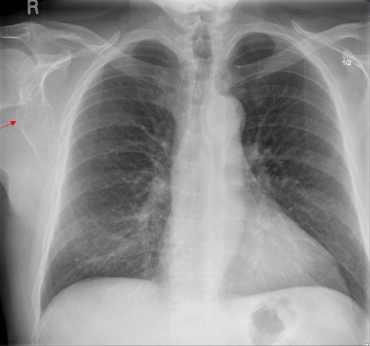

Pancoast Tumor on X-ray